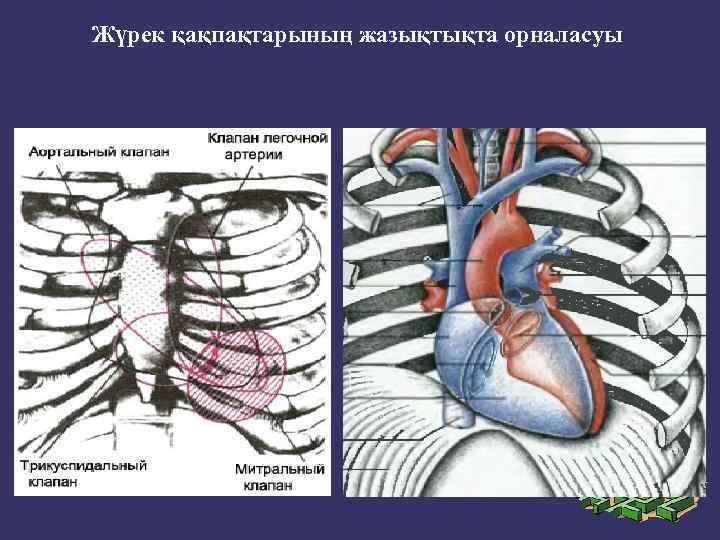

Митральды қақпақ (сол жақ жүрекше - қарыншалық қақпақ) төстің III қабырғамен түйіскен жерінде проекцияланады. Қолқа қақпағы төстің III қабырғаның сол және оң жақтарындағы шеміршектерінің бекіністерінің ортасынан жүргізілген сызықтың ортасында проекцияланады.

Жүрек қақпақтарының жазықтықта орналасуы